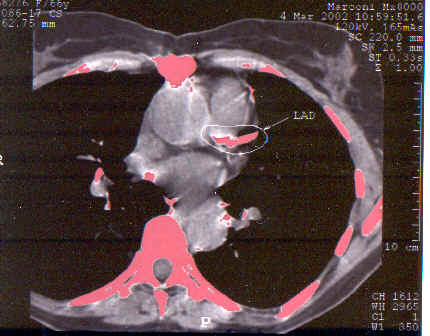

# 3 FL: Avoiding Angiography in an Octogenarian

This turned out to be a good

idea. FL tolerated four months of

NanobacTX well; angina frequency fell from 5 to 1 episode per week, NTG is no

longer required, and FL was able to increase her activity level considerably.

Her CT score fell by 26%, fibrinogen fell by 30 points, and her

cardiac-CRP value plummeted. Following an additional two months of treatment, FL's score

fell an additional 36%, so at the six month point, FL's score has fallen by

53% from baseline. A dobutamine stress echo (chemical stress echo)

demonstrated the old heart attack that we knew about, but no new abnormalities

were brought out. Subjectively and objectively FL improved. The

baseline and six month scans are shown below; with your own eye you can see the

difference in the extent of LAD calcification. FL is going to continue on NanobacTX, aiming for

complete decalcification.